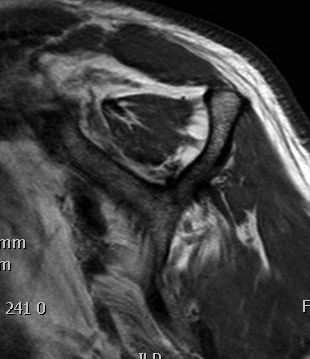

Goutallier classification

Amount of fatty degeneration in rotator cuff muscle belly on a T1 sagittal MRI

Some fatty streaks MRI shows some fatty streaks in supraspinatus |

More muscle than fat MRI shows grade 2 in supraspinatus |

Equal fat and muscle MRI demonstrates grade 3 supraspinatus and infraspinatus |

More fat than muscle MRI demonstrates grade 4 infraspinatus |

Examples of rotator cuff tears that are likeley irreparable